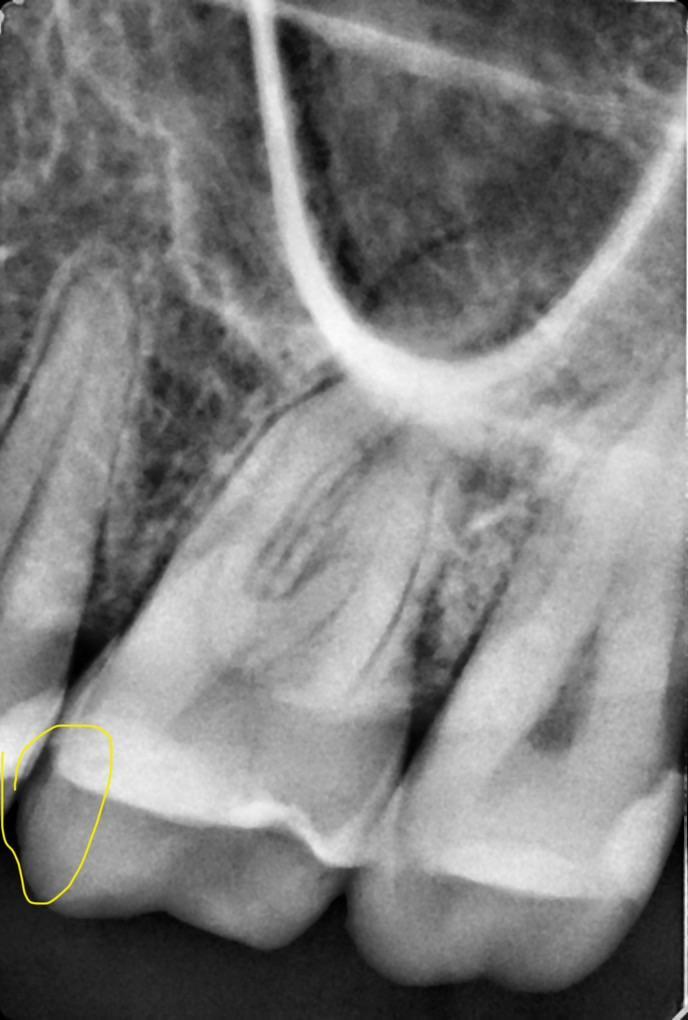

muffin, похоже на кариес в пятёрке!?

21017fc249d0359261ca4d9db6b1.jpg

если ощущение дырки между пятым и шестым, то это ОНО!

В прошлый раз мне запломбировали этот зуб Здесь, там, где я его отметила, я чувствую его языком, там углубление, и пища сразу попадает внутрь.

muffin, ну, значит я не ошибся - в пятёрке кариес, только он под десной и виден только на рентген-снимке...